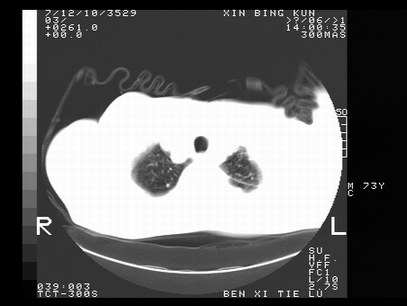

标题: CT10820:男,73岁,病史肺TB,现病史肺炎,直肠CA术后 [打印本页]

标题: CT10820:男,73岁,病史肺TB,现病史肺炎,直肠CA术后

双肺间质改变,依据病史双肺多发结节灶考虑转移,少量胸水.

1.两肺结核.2.两肺多发转移瘤.3右侧少量胸腔积液4.主动脉钙化.

双肺多发结节及条片状致密影,右侧少量胸腔积液。临床:直肠ca术后,肺tb病史。综合考虑:1 双肺转移!2 继发性肺结核合并感染!

此人病史较复杂,原有肺结核,直肠癌术后。肺部病灶形态亦呈多形性。因此,不可仅以一种病来解释肺部的病变。双肺多发的类圆形结节灶,结合病史还是首先考虑转移瘤,而双肺其余病灶还需结合化验室检查,结核或肺部感染在无其它检查资料的情况下不好排除。还是那句话----放射科医生不是开照像馆的,我们也是医生,看片一定要多结合临床及其它检查资料。要当一名合格的放射科医生,并不比当一名临床医生容易,我们可别把自已不当医生看。

两肺多发结节影,并见滋养动脉与其相连,考虑 两肺转移. 右侧胸腔积液考虑胸膜转移.

左肺上叶下叶背段,右肺中下叶见多发斑片状、条索状高密度影,兵变周围小结节影形成“树芽”样改变。 左肺上叶舌段近前胸壁处及右肺中叶内侧段见结节影。右侧胸膜腔内见液体密度区。纵隔内未见明确增大淋巴结。考虑左肺上叶舌段近前胸壁处及右肺中叶转移瘤可能性大。两肺继发型肺结核。右侧胸腔积液。